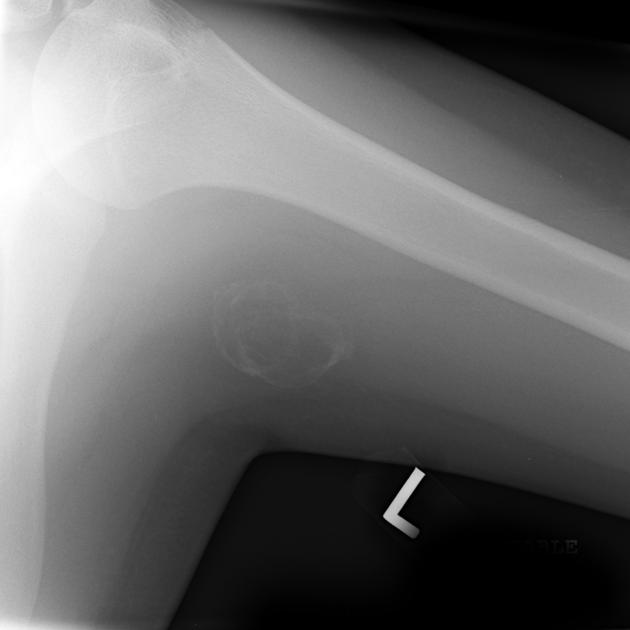

CT may be useful in the visualization of a lesion. Figure 3 demonstrates a lesion posterior to the right acetabulum. It demonstrates a partially corticated periphery and partial cleft separating the lesion from the acetabulum. Figure 4 is an interesting example of an MO lesion in the paraspinal musculature, with ossified periphery and lucent center.